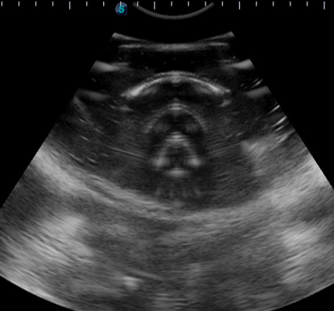

部分容积效应

声束的宽度不可忽略,如果有小于切片厚度的病灶被切割,则图上表现为既有病灶又有周围区的重叠回声图